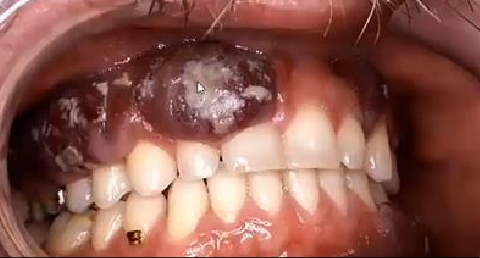

Q

A

Candidiasis oral sobre

sarcoma de Kaposi en

paciente HIV